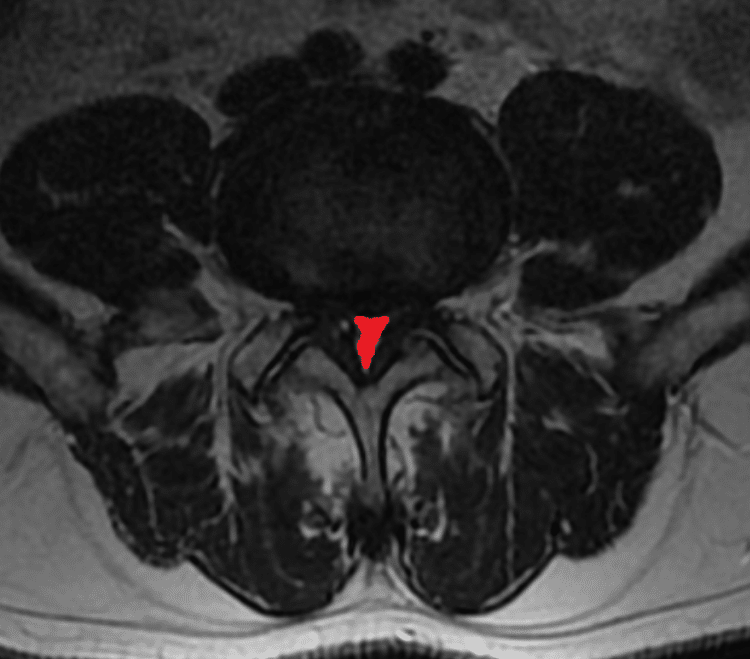

Obraz ciasnoty kanału kręgowego

Powierzchnia mocno zwężonego kanału kręgowego w przebiegu ciasnoty (zaznaczona na czerwono)